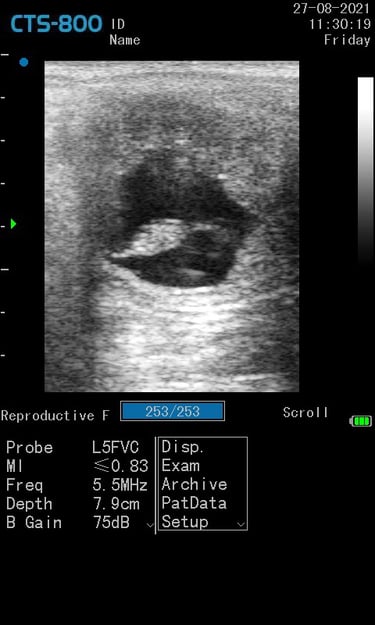

Gynécologie